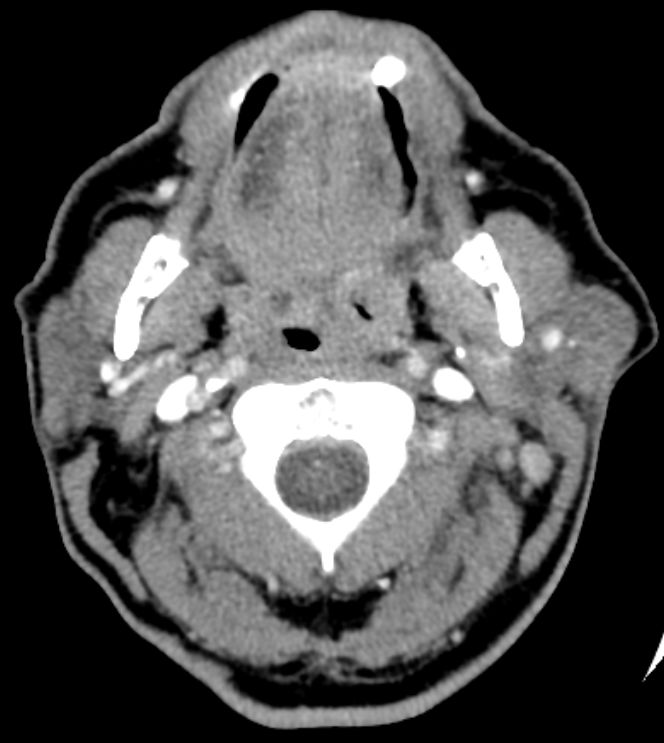

64-jähriger Mann mit tumoröser Raumforderung der linken Tonsille. Die primäre Histologie war verdächtig auf ein entdifferenziertes p16-positives Plattenepithelkarzinom. Bei der Radikaloperation wurden 84 Lymphknoten der Level 2-4 beiderseits entfernt, von denen 55 metastatisch befallenen waren. Zusätzlich wurde ein nicht zugänglicher Lymphknoten unterhalb der Karina festgestellt. Die transösophageale Punktion dieses Lymphknotens ergab den Verdacht eines malignen Lymphoms. Daraufhin wurden von den zervikalen Lymphnoten zusätzliche immunhistochemische Untersuchungen durchgeführt. Nach Vorliegen der Referenzpathologie handelt es sich um den seltenen Fall eines sarkomatoiden Lymphom oder eines histiozytischen Sarkoms. Diese Zellen sehen einem entdifferenzierten Plattenepithelkarzinom sehr ähnlich. | ||

Zahlreiche vergrößerte zervikale Lymphknoten.![]() |